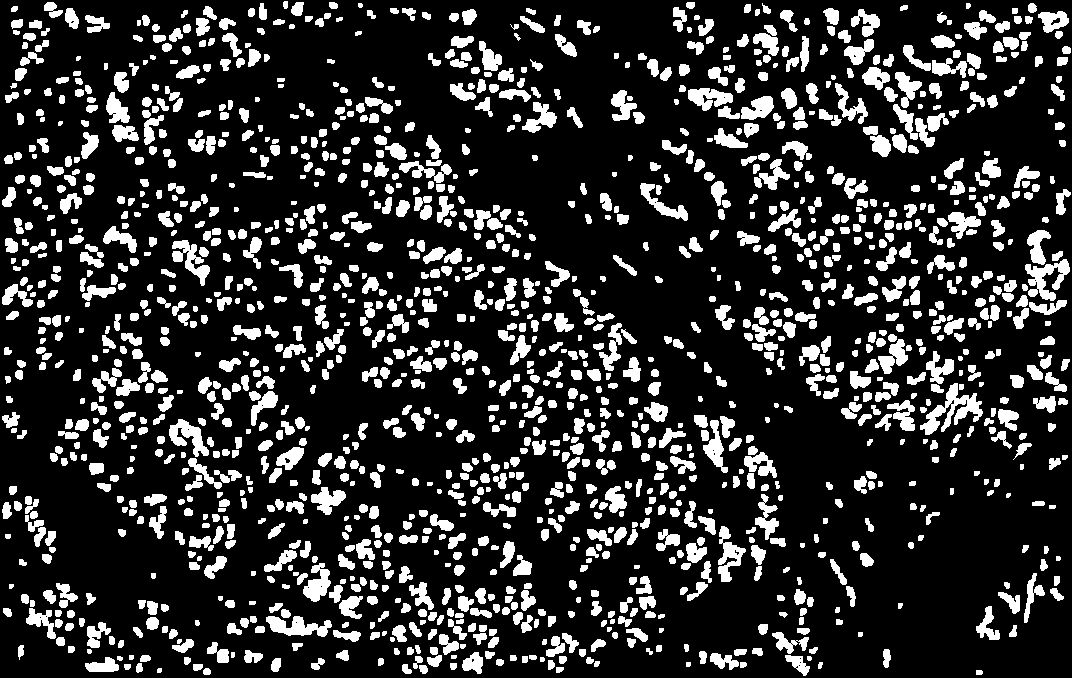

I used support vector machines (SVM) to develop a machine learning model that accurately predicts whether a breast cancer patient is likely to experience a recurrence after treatment. The prognosis method examines the patient's biopsy slide image with computer vision and leverages complex statistical methods to analyze the expression values of thousands of genes.